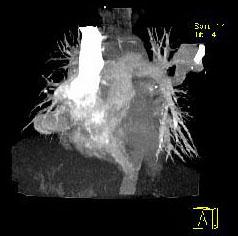

问题 男性,26岁,头晕、气逼三年余,CT检查如图所示,请选择的最可能诊断 ( )

选项 A、动静脉畸形 B、动脉瘤 C、毛细血管扩张症 D、毛细血管瘤 E、海绵状血管瘤

答案 A